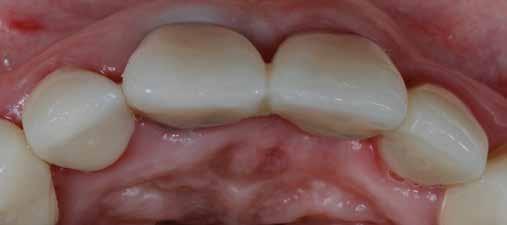

A rendelésünkön egy 34 éves latin-amerikai nőbeteg azzal a panasszal jelentkezett, hogy a fogait „túl rövidnek” találja, és ezen felül a mosolyával sem volt megelégedve. Az anamnézisfelvétel alapján egészséges volt, elmondása szerint rendszeresen járt orvoshoz. Öt évvel korábban néhány hátsó fogát restaurálták. Páciensünk szájhigiénéje megfelelő volt,

a fogait rendszeresen ápolta. House klasszifikációja szerint, amely a pácienseket a fogászati kezelésekhez való attitűdjük szerint négy csoportba sorolja, a páciensünk a szabálykövető csoportba tartozott.

Az előzetes állapotfelmérést és a kezelés megtervezését követően a fogakat minimál invazív módon preparáltuk (1. a-b ábrák), majd az előkészített fogak ínybarázdáiba fonalbehelyező eszköz segítségével (113 Serrated Gingival Cord Packer, Hu-Friedy, Chicago, Illinois) teflonszalagot helyeztünk (Loctite Thread Seal Tape, Henkel Loctite Corp., Egyesült Államok), (1. c ábra). A hagyományos retrakciós fonalak helyett, a rugalmasságuk miatt előnyösebbnek tartjuk a teflonszalagok használatát. A kofferdámot (Dental Dam, Nic Tone, Bukarest, Románia) az előkészített fogakon kívül, az azoktól disztálisan elhelyezkedő egy-egy fognak megfelelően is perforáltuk.

Az oxigén inhibíciós réteg kialakulásának elkerülése érdekében a kerámiafelszíneket glicerin géllel (Liquid Strip, Ivoclar Vivadent, Schaan, Liechtenstein) borítottuk, majd ezeket a felszíneket ismét 20-20 másodpercen keresztül világítottuk. A végeredmény megfelelt a páciens esztétikai igényeinek (6. a. ábra). Az átadott restaurátumok épségének megőrzése érdekében, a páciens számára éjszakai fogvédő sín készült. Az ötéves kontroll alkalmával megállapítottuk, hogy az elvégzett kezelésünk továbbra is sikeresnek tekinthető (6. b. ábra)